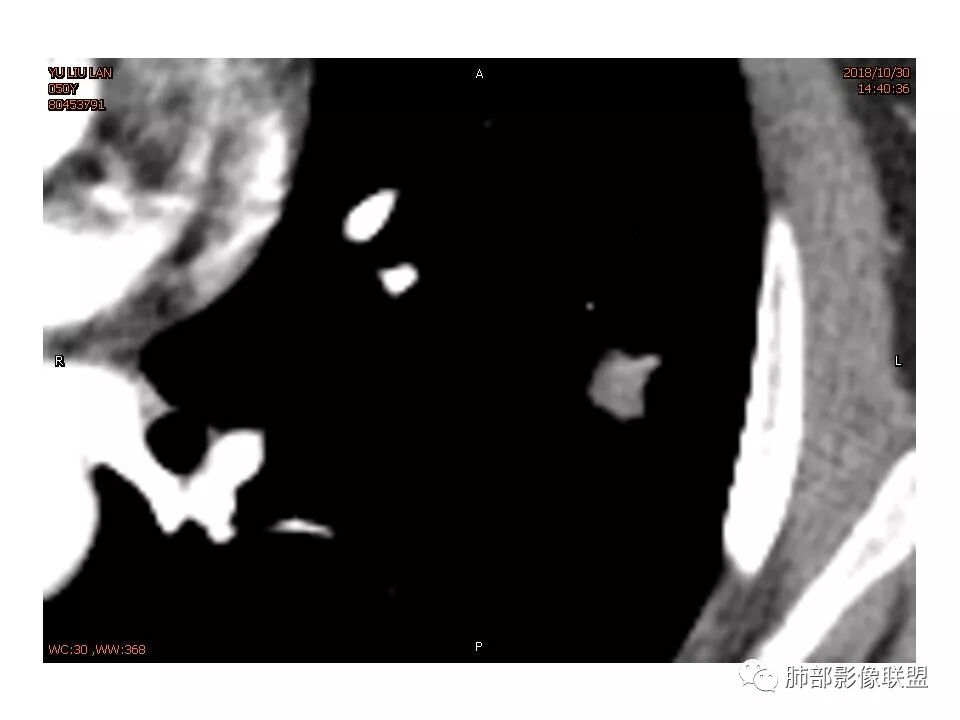

女,50。实性不规则结节,大小12*13mm,分叶、毛刺、胸膜凹陷,牵拉力强,增强渐进性强化,动脉期强化20,静脉期还有进一步强化。边缘强化,点状坏死。

尽管有收缩性改变,但是部分层面可见病灶有膨胀性表现,增强后病灶内可见血管影,局部血管凹凸不平,再加上病灶的分叶,胸膜凹陷征象等等,是不能排除恶性病变,写报告时,仍然需要把恶性病变靠前,腺癌第一考虑,其次炎性肌纤维母,再次再考虑炎性病变。

血管贴边,但没有明显压迫征象。明显强化。局部膨隆,毛刺,分叶。

胸膜牵拉,这些都支持恶性

恶性征像,胸膜牵拉,浅分叶,毛刺,增强强化明显,净增超25hu。血管边缘模糊串珠样改变。

细小毛刺,梳状平行,周围边缘模糊晕,血管未收侵犯,支气管未见牵拉扩张,多条淋巴道与胸膜相联,倾向于炎性病变